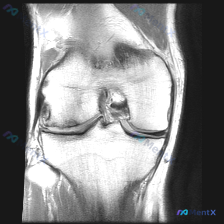

都说软骨有异常,但单张膝关节MRI居然全正常?这个矛盾怎么处理

今天遇到一个挺典型的临床情况,整理出来和大家聊聊:核心问题是临床观察提示「软骨异常」,但我们拿到的单幅膝关节MRI冠状位T2加权像分析却全是阴性结果,一起来理理思路。

先给大家放完整影像信息:

- 整体结构对位:股骨远端胫骨近端对位正常,无骨折错位

- 骨髓信号:股骨髁、胫骨平台骨髓信号大致均匀,无明显异常高信号水肿或局灶病变

- 关节间隙:内外侧间隙大致等宽,无局限性狭窄

- 半月板:内外侧半月板形态都正常,无异常高信号延伸到关节面,也没有结构中断

- 韧带:内外侧副韧带、前交叉韧带都连续,信号正常,无水肿或中断

- 关节软骨&软骨下骨:股骨髁和胫骨平台软骨轮廓连续,没有局灶软骨缺损,也没有软骨下骨破坏

- 关节腔&软组织:没有大量积液,周围软组织信号正常